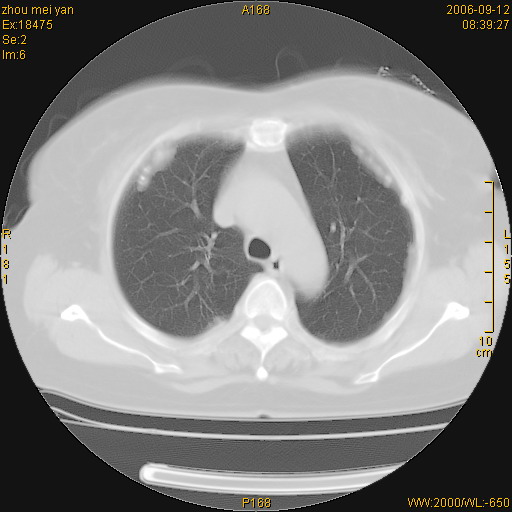

患者、女、55岁。因心率失常住院检查ct发现胸部多发结节。腹部b超肝、胆、胰、脾、肾、子宫附件未见异常。无结核病史,无粉尘接触史。请大家来会诊。谢谢!

病变位于胸膜,多发结节,边界清楚,内见小结节状钙化。其它未见异常。

多发胸膜表面的结节,基本对称,部分有钙化。首先考虑类风湿性胸膜结节,次则考虑结核性胸膜炎后遗之胸膜结节状增厚、钙化。

双侧胸膜多发结节,形态不规则,边缘较清楚,每一个结节中心似乎都有钙化点的特征,与胸膜广基相切。临床无结核病史,无粉尘接触史。

影像表现十分有特点:双侧肋胸膜及膈胸膜广泛散在分布大小在2至6mm左右,较大病灶中心可见钙化。

双侧肋胸膜及膈胸膜广泛散在分布大小不等结节影,较大病灶中心可见钙化。